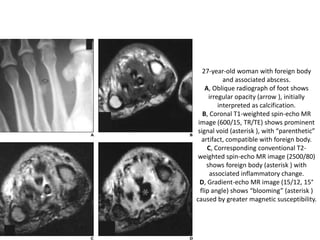

27-year-old woman with foreign body

and associated abscess.

A, Oblique radiograph of foot shows

irregular opacity (arrow ), initially

interpreted as calcification.

B, Coronal T1-weighted spin-echo MR

image (600/15, TR/TE) shows prominent

signal void (asterisk ), with “parenthetic”

artifact, compatible with foreign body.

C, Corresponding conventional T2-

weighted spin-echo MR image (2500/80)

shows foreign body (asterisk ) with

associated inflammatory change.

D, Gradient-echo MR image (15/12, 15°

flip angle) shows “blooming” (asterisk )

caused by greater magnetic susceptibility.